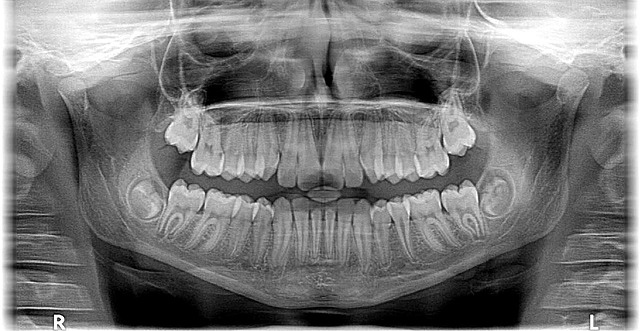

In McAllen, Texas, a leading edge in dental care is brought forth by dedicated orthodontists who understand that a beautiful smile is more than aesthetic—it’s a catalyst for confidence and personal growth. These specialists, armed with the latest advancements in orthodontic technology, are committed to not just straightening teeth but enhancing patients’ overall well-being. By prioritizing personalized treatment plans tailored to individual needs, they ensure every patient leaves satisfied and proud of their transformed smile.

Whether it’s addressing mild alignment issues or complex cases requiring intensive care, McAllen orthodontists offer a range of options from traditional braces to innovative clear aligner systems. Accessible through convenient appointments at 956-686-5000, these professionals foster an environment where patients can openly discuss their concerns and goals. Just dial 956-686-5000 to schedule an appointment and experience the difference a McAllen orthodontist can make in your life.